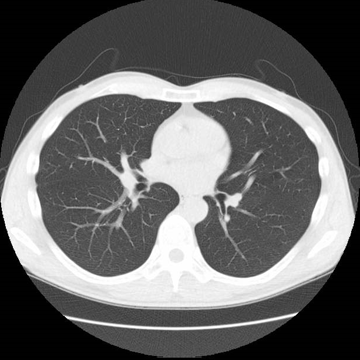

まずは、位置決めの写真をとります。

次に、輪切りの写真をとります。

もう一度、機械の音声で呼吸の合図をします。

1回目より少し長い時間(10秒程度)の息止めが必要になります。